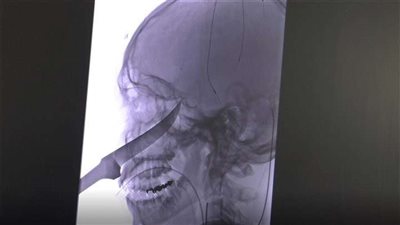

بالصور.. إنقاذ شاب بعد اختراق سكين بطول 23 سنتيمتر لجمجمته